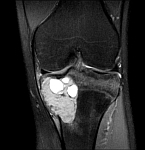

• Tumor surgery of the musculoskeletal system

• Resection of benign and malignant tumors of the bone and soft tissue